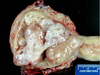

Q

A

Where is the submucosal leiomyoma in this picture? What about the intramural leiomyoma?

A